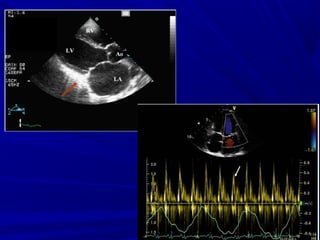

ECHO-CARDIOGRAPHYECHO-CARDIOGRAPHY

Thick pericardium/calcifiedThick pericardium/calcified

““Small ventricles”Small ventricles”

““Big atria”Big atria”

IVC distension, hepatic veins distensionIVC distension, hepatic veins distension